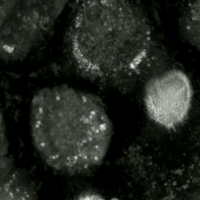

Live-cell imaging has been used to observe the morphological changes that cells undergo during oxytosis/ferroptosis. Initially the cell contracts and then begins to swell. Perinuclear lipid assembly is observed immediately before oxytosis/ferroptosis occurs. After the process is complete, lipid droplets are redistributed throughout the cell (see GIF on right side). [citation needed]